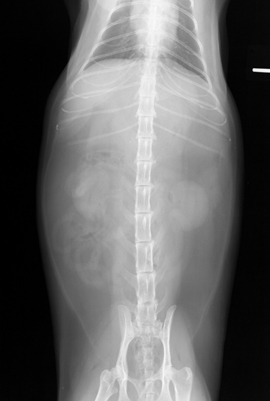

Lateral view of a normal feline abdomen.